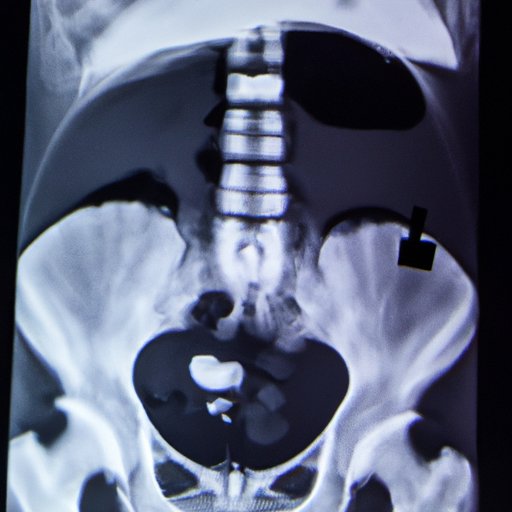

A Hida Scan, also known as cholescintigraphy, is a medical imaging test that helps visualize the liver, gallbladder, and bile ducts. It is used to diagnose various conditions, including gallbladder problems, bile duct obstruction, and liver diseases. During the procedure, a small amount of radioactive material is injected into the bloodstream, which is later absorbed by the liver and secreted into the bile. The radioactive material then flows with the bile through the ducts and into the gallbladder, where it is detected by a gamma camera, which generates images of these organs.

During the procedure, patients lie on their back on a table with a gamma camera above them. A technician will then inject the radioactive material through a vein in their arm. Images will be taken at different intervals, typically every 15-20 minutes, up to a total of 2 hours. Patients may be asked to take deep breaths, change positions, or move as required to get a clear image.